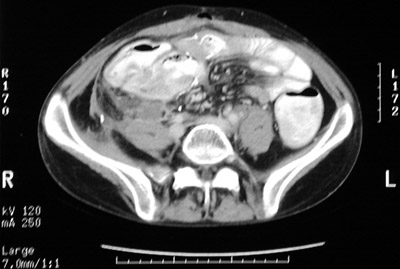

| Here are two views of an abdominal CT scan which reveal inflammatory changes in the right lower quadrant in the region of the cecum that resulted from neutropenic colitis. This immunocompromised state, which can occur with leukemia, chemotherapy, and other conditions that reduce the number of neutrophils, predisposes to inflammation, particularly in the region of the cecum. |